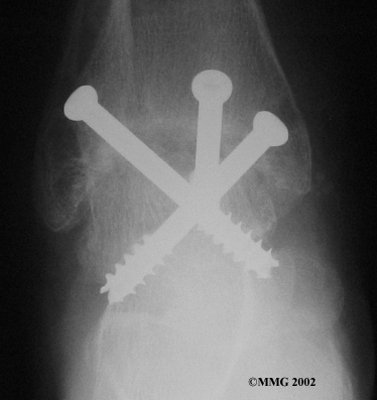

It is important when the surfaces are removed that the angles of the cut surfaces are correct. When the tibia is brought against the talus, the foot should be at a right angle to the lower leg. Once the cuts are made the bones must be held in place while they fuse. This can be done using large metal screws and metal plates if necessary. The screws are usually under the skin and are not removed unless they begin to rub and cause pain.